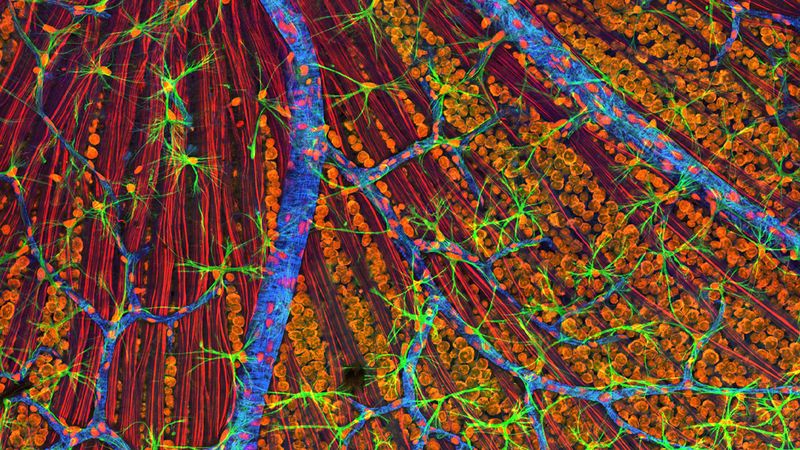

The rest of this article is behind a paywall. Please sign in or subscribe to access the full content.The research, published in the journal Cell, focused on glial cells in the brain, which help hold neurons in places, deliver nutrients to neurons, and assist in the synaptic connections between nerve cells. It appears that the glial cells of people who suffer from childhood-onset schizophrenia were highly dysfunctional and weren’t able to perform their functions.

The team extracted skin cells from individuals with pediatric schizophrenia and turned those cells into induced pluripotent stem cells, which have the ability to turn into any type of cell. The researchers forced them to develop into glial progenitor cells (GPCs), which are the “parent” cells for two kinds of glia – astrocytes and oligodendrocytes. The former are support cells, while the latter produce myelin – a fatty substance that acts as an insulator for neurons.

These GPCs were transplanted into the brains of neonatal mice and out-competed the mice's own GPCs. Mice that received the faulty cells developed schizophrenic-type symptoms and behaviors. An analysis of their brain structure showed that the development of astrocytes and oligodendrocytes was delayed, causing signaling between neurons to become severely impaired.

"The astrocytes didn't fully mature and their fibers did not fill out their normal domains, meaning that while they provided control to some synapses, others had no coverage," first author Dr Martha Windrem, from URMC's Center for Translational Neuromedicine, added. "As a result, the neural networks in the animals became desynchronized and uncoordinated."